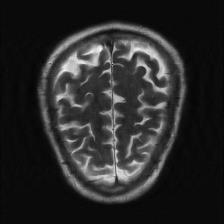

Recently, deep neural networks have greatly advanced undersampled Magnetic Resonance Image (MRI) reconstruction, wherein most studies follow the one-anatomy-one-network fashion, i.e., each expert network is trained and evaluated for a specific anatomy. Apart from inefficiency in training multiple independent models, such convention ignores the shared de-aliasing knowledge across various anatomies which can benefit each other. To explore the shared knowledge, one naive way is to combine all the data from various anatomies to train an all-round network. Unfortunately, despite the existence of the shared de-aliasing knowledge, we reveal that the exclusive knowledge across different anatomies can deteriorate specific reconstruction targets, yielding overall performance degradation. Observing this, in this study, we present a novel deep MRI reconstruction framework with both anatomy-shared and anatomy-specific parameterized learners, aiming to "seek common ground while reserving differences" across different anatomies.Particularly, the primary anatomy-shared learners are exposed to different anatomies to model flourishing shared knowledge, while the efficient anatomy-specific learners are trained with their target anatomy for exclusive knowledge. Four different implementations of anatomy-specific learners are presented and explored on the top of our framework in two MRI reconstruction networks. Comprehensive experiments on brain, knee and cardiac MRI datasets demonstrate that three of these learners are able to enhance reconstruction performance via multiple anatomy collaborative learning.

翻译:最近,深心神经网络大大推进了未经充分取样的磁共振成像(MRI)重建,其中大多数研究都遵循单一解剖一个网络的方式,即每个专家网络都经过特定解剖学的培训和评价。除了在培训多种独立模型方面效率低下之外,这种公约忽视了不同解剖学中共享的、可相互受益的解析知识。为了探索共享知识,一种天真的方法是将各解剖学家的所有数据结合起来,以训练一个全方位网络。不幸的是,尽管存在共享的解析知识,但我们发现,不同解剖学的独家知识可以恶化具体的重建目标,导致总体性能退化。在这项研究中,我们提出了一个新型的深度解剖重建框架,既有解剖学共享知识,又具有具体的解剖学参数,目的是“寻找共同的土壤,同时保留不同解剖学家之间的差异。此外,主要的解剖学学习者将接触不同的解剖学数据,通过多种解剖学重建的模型,并用不同的解剖学研究者将数据展示出一个全方位基础。